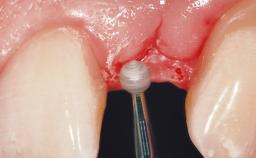

A 39-year-old male patient presented with a chief complaint of discomfort and gingival discoloration around his maxillary left central incisor. He was in good general health and was a non-smoker. His past dental history was significant because of the traumatic fracture of tooth 21 in a sporting accident at age 13. Initial dental treatment included endodontic therapy and a full-coverage restoration. The patient became symptomatic 5 years later, when structural failure of the tooth resulted in the dislodgment of the crown. Endodontic retreatment, apical surgery, and post-and-core restoration were performed.

Bone Augmentation Horizontal|Staged

Augmentation Materials Xenogenous|Membrane

Soft Tissue Grafting Simultaneous